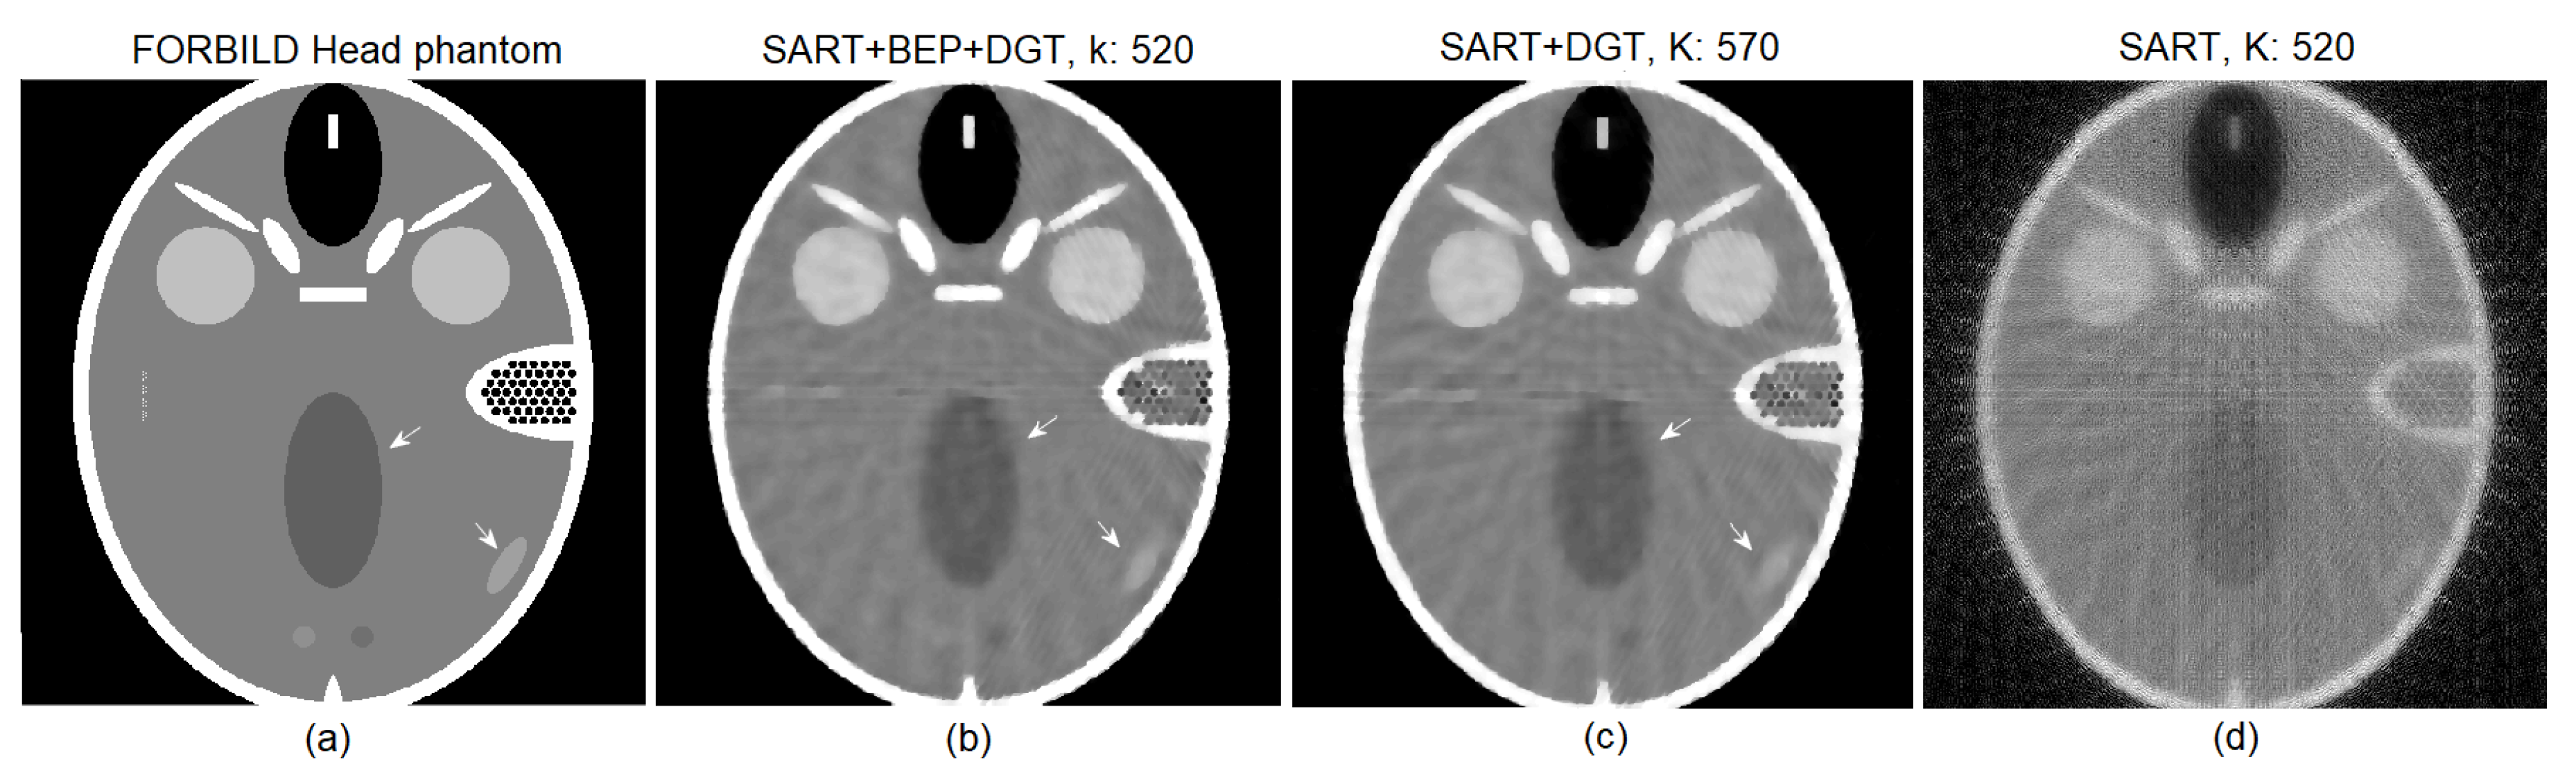

4. Experiments and Results

Low Dosage Tests and Results